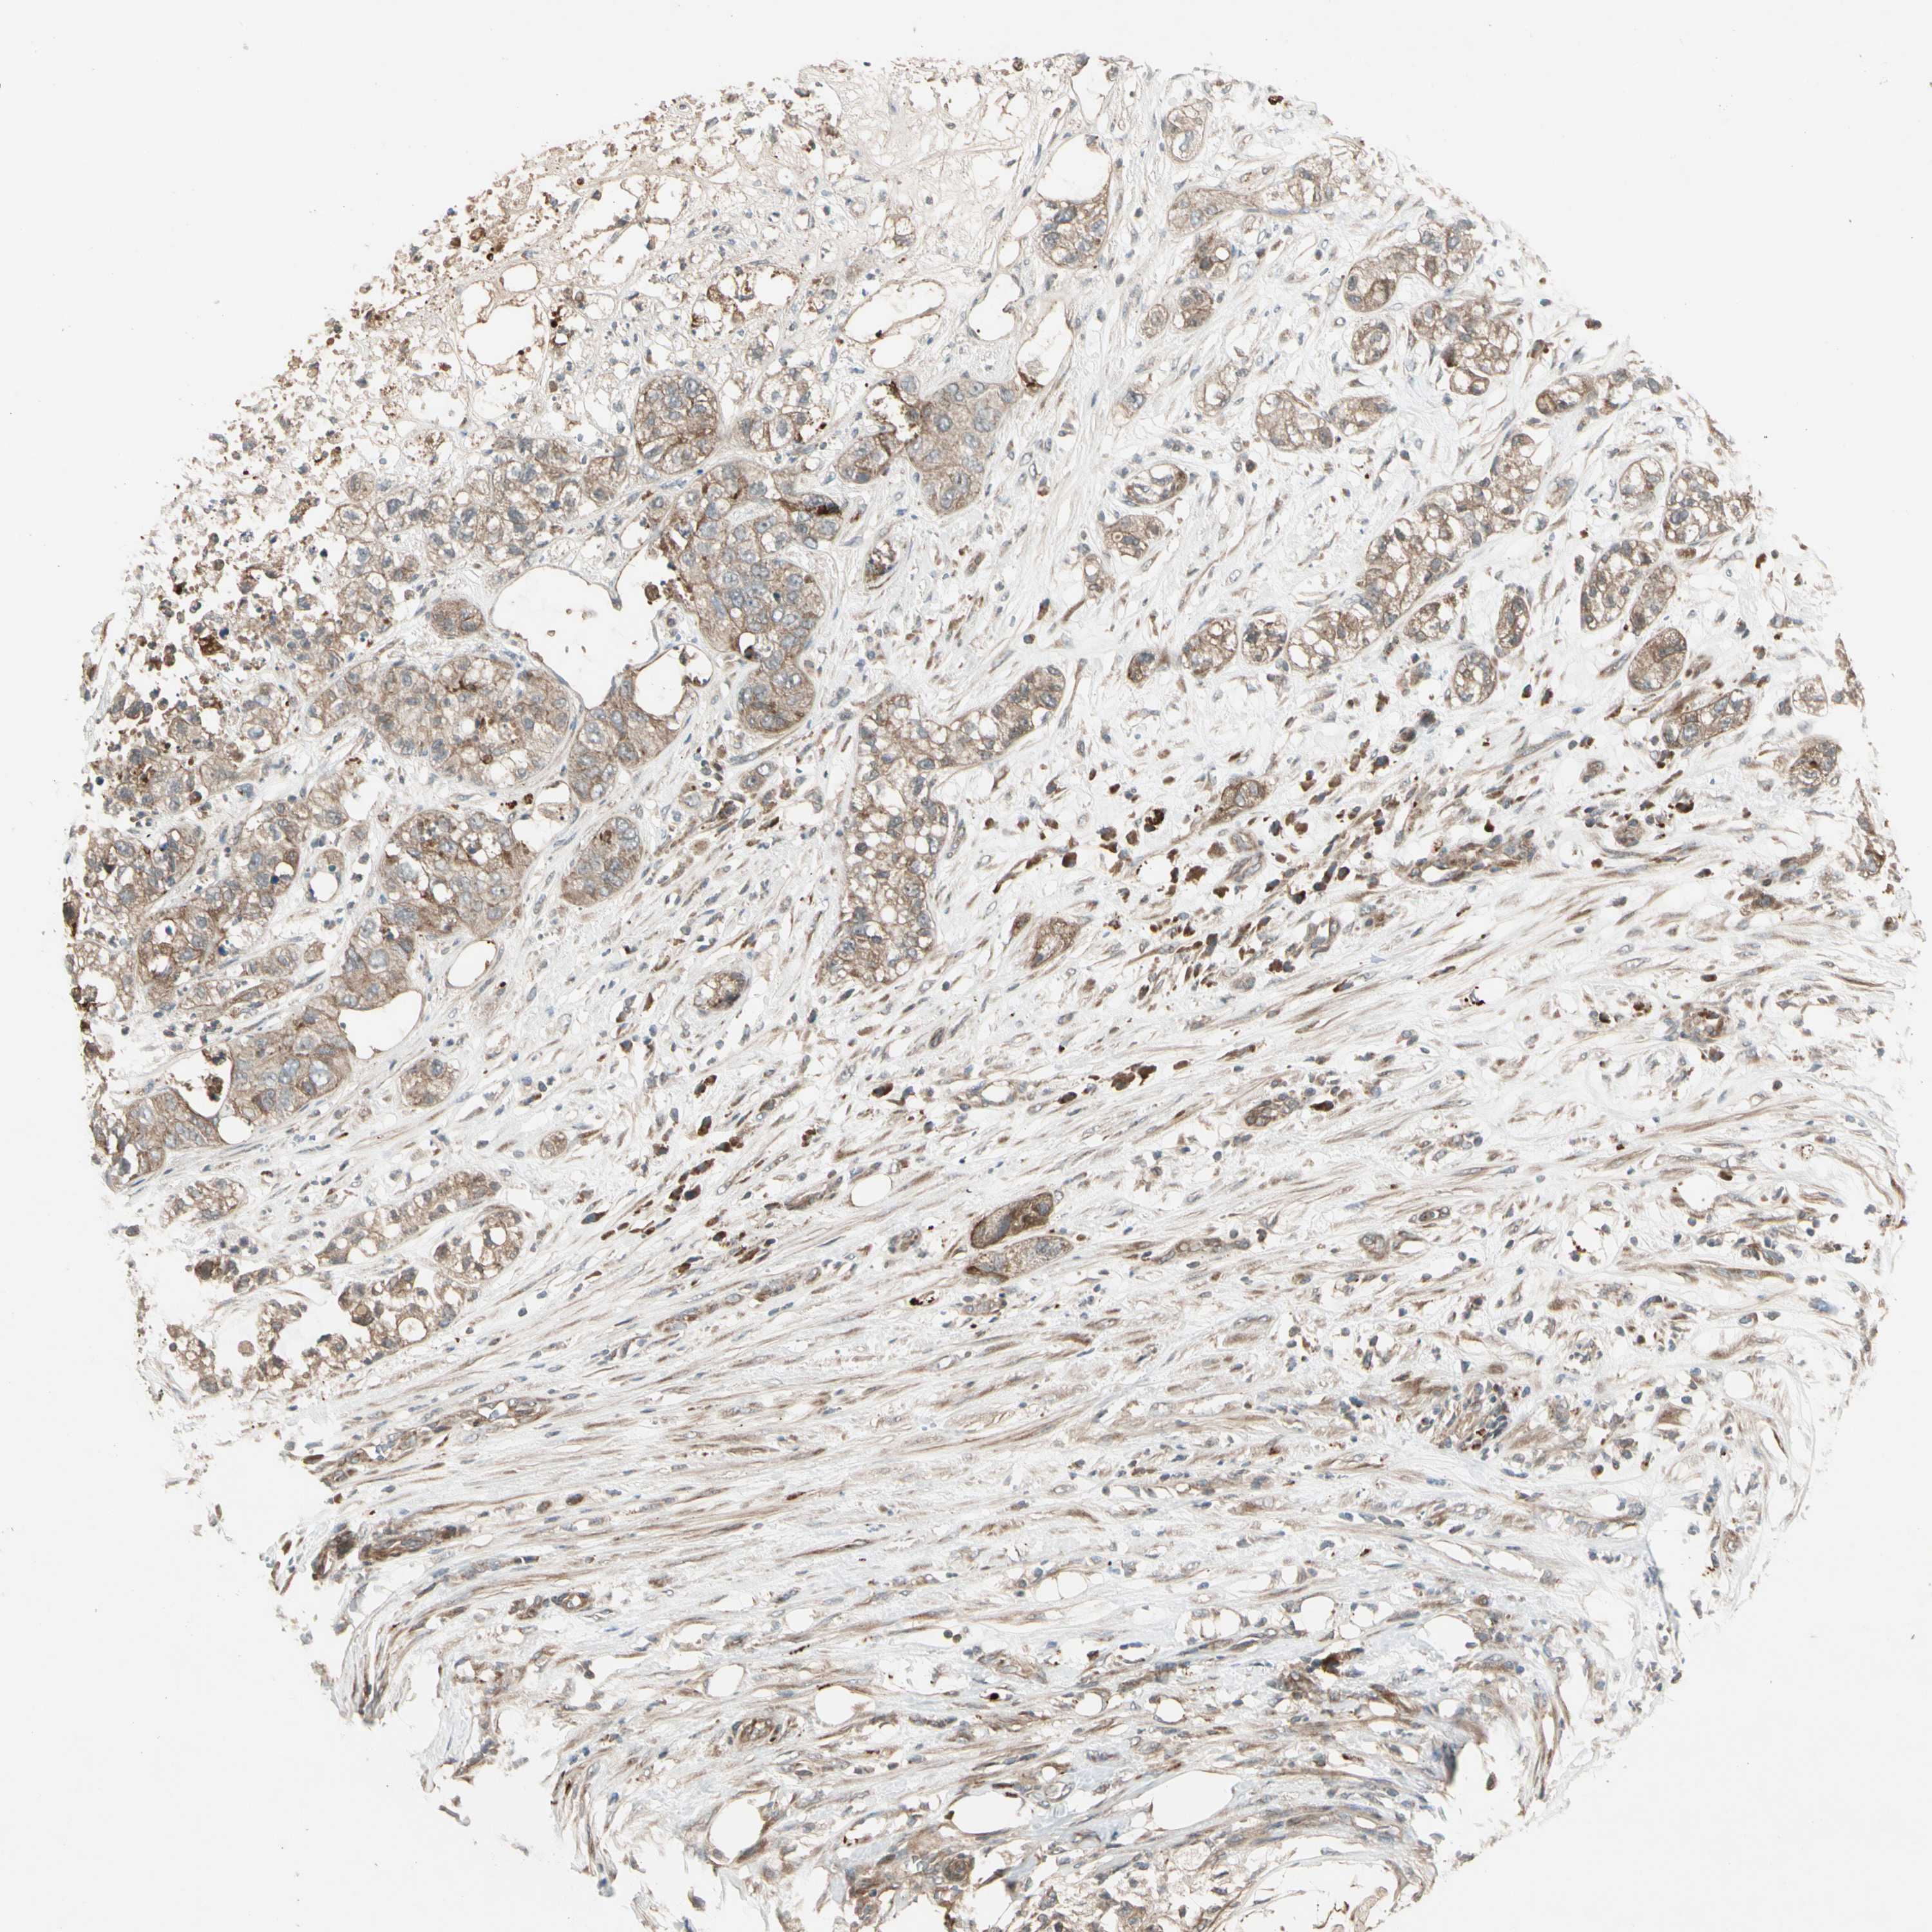

PANCREATIC CANCER - Protein expressioni

A mouse-over function shows sample information and annotation data. Click on an image to view it in a full screen mode. Samples can be filtered based on level of antibody staining by selecting one or several of the following categories: high, medium, low and not detected. The assay and annotation is described here.

Note that samples used for immunohistochemistry by the Human Protein Atlas do not correspond to samples in the TCGA dataset.

Antibody stainingi

Antibody staining in the annotated cell types in the current human tissue is reported as not detected, low, medium, or high, based on conventional immunohistochemistry profiling in selected tissues. This score is based on the combination of the staining intensity and fraction of stained cells.

Each image is clickable and will lead to virtual microscopy that enables deeper exploration of all samples and also displays staining intensity scores, fraction scores and subcellular localization as well as patient and tissue information for each sample.

Antibody HPA007982

Antibody HPA011933

Staining

High

Medium

Low

Not detected

Intensity

Strong

Moderate

Weak

Negative

Quantity

>75%

75%-25%

<25%

None

Location

Nuclear

Cytoplasmic/membranous

Cytoplasmic/membranous,nuclear

Adenocarcinoma, NOS

Adenocarcinoma, metastatic, NOS